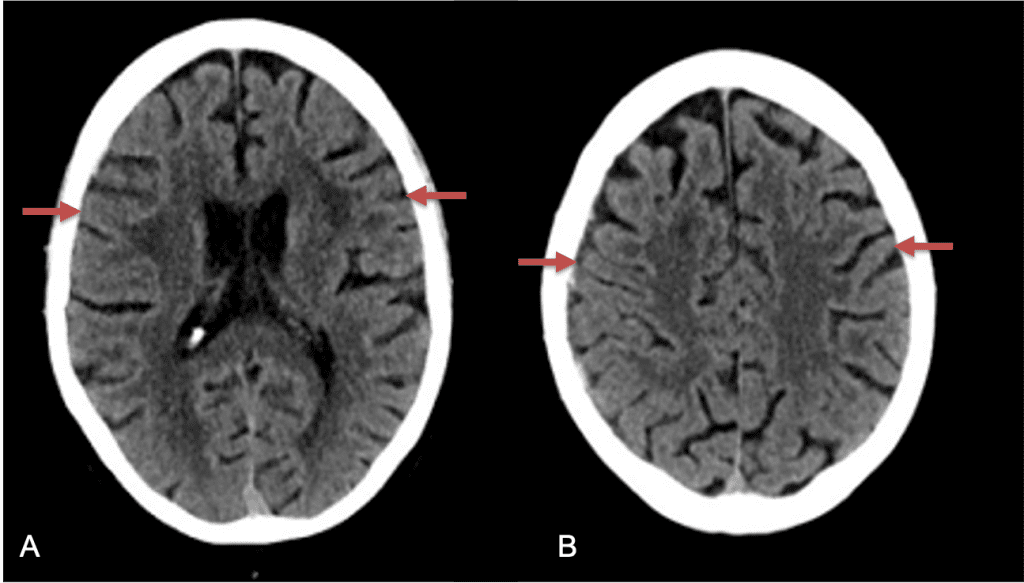

A woman in her 80s developed mild dizziness and headache following incidental trauma working in her garage one day. She presented several weeks later to the ER and was diagnosed with bilateral subdural hematomas, which were initially managed with observation, low dose Decadron, considering the mildness of symptoms, advanced age, and history of CLL with thrombocyptopenia (<100k). Over the next 4 weeks, the collections remained relatively stable with evidence of slight growth (10 to 12 mm thickness, and 2 mm right to left shift) on NCT (Figure 1. A and B).

Figure 1. A) 6 weeks post mild trauma B) 4 weeks post mild trauma demonstrates stable subacute subdural collections with mild growth and sulcal effacement.